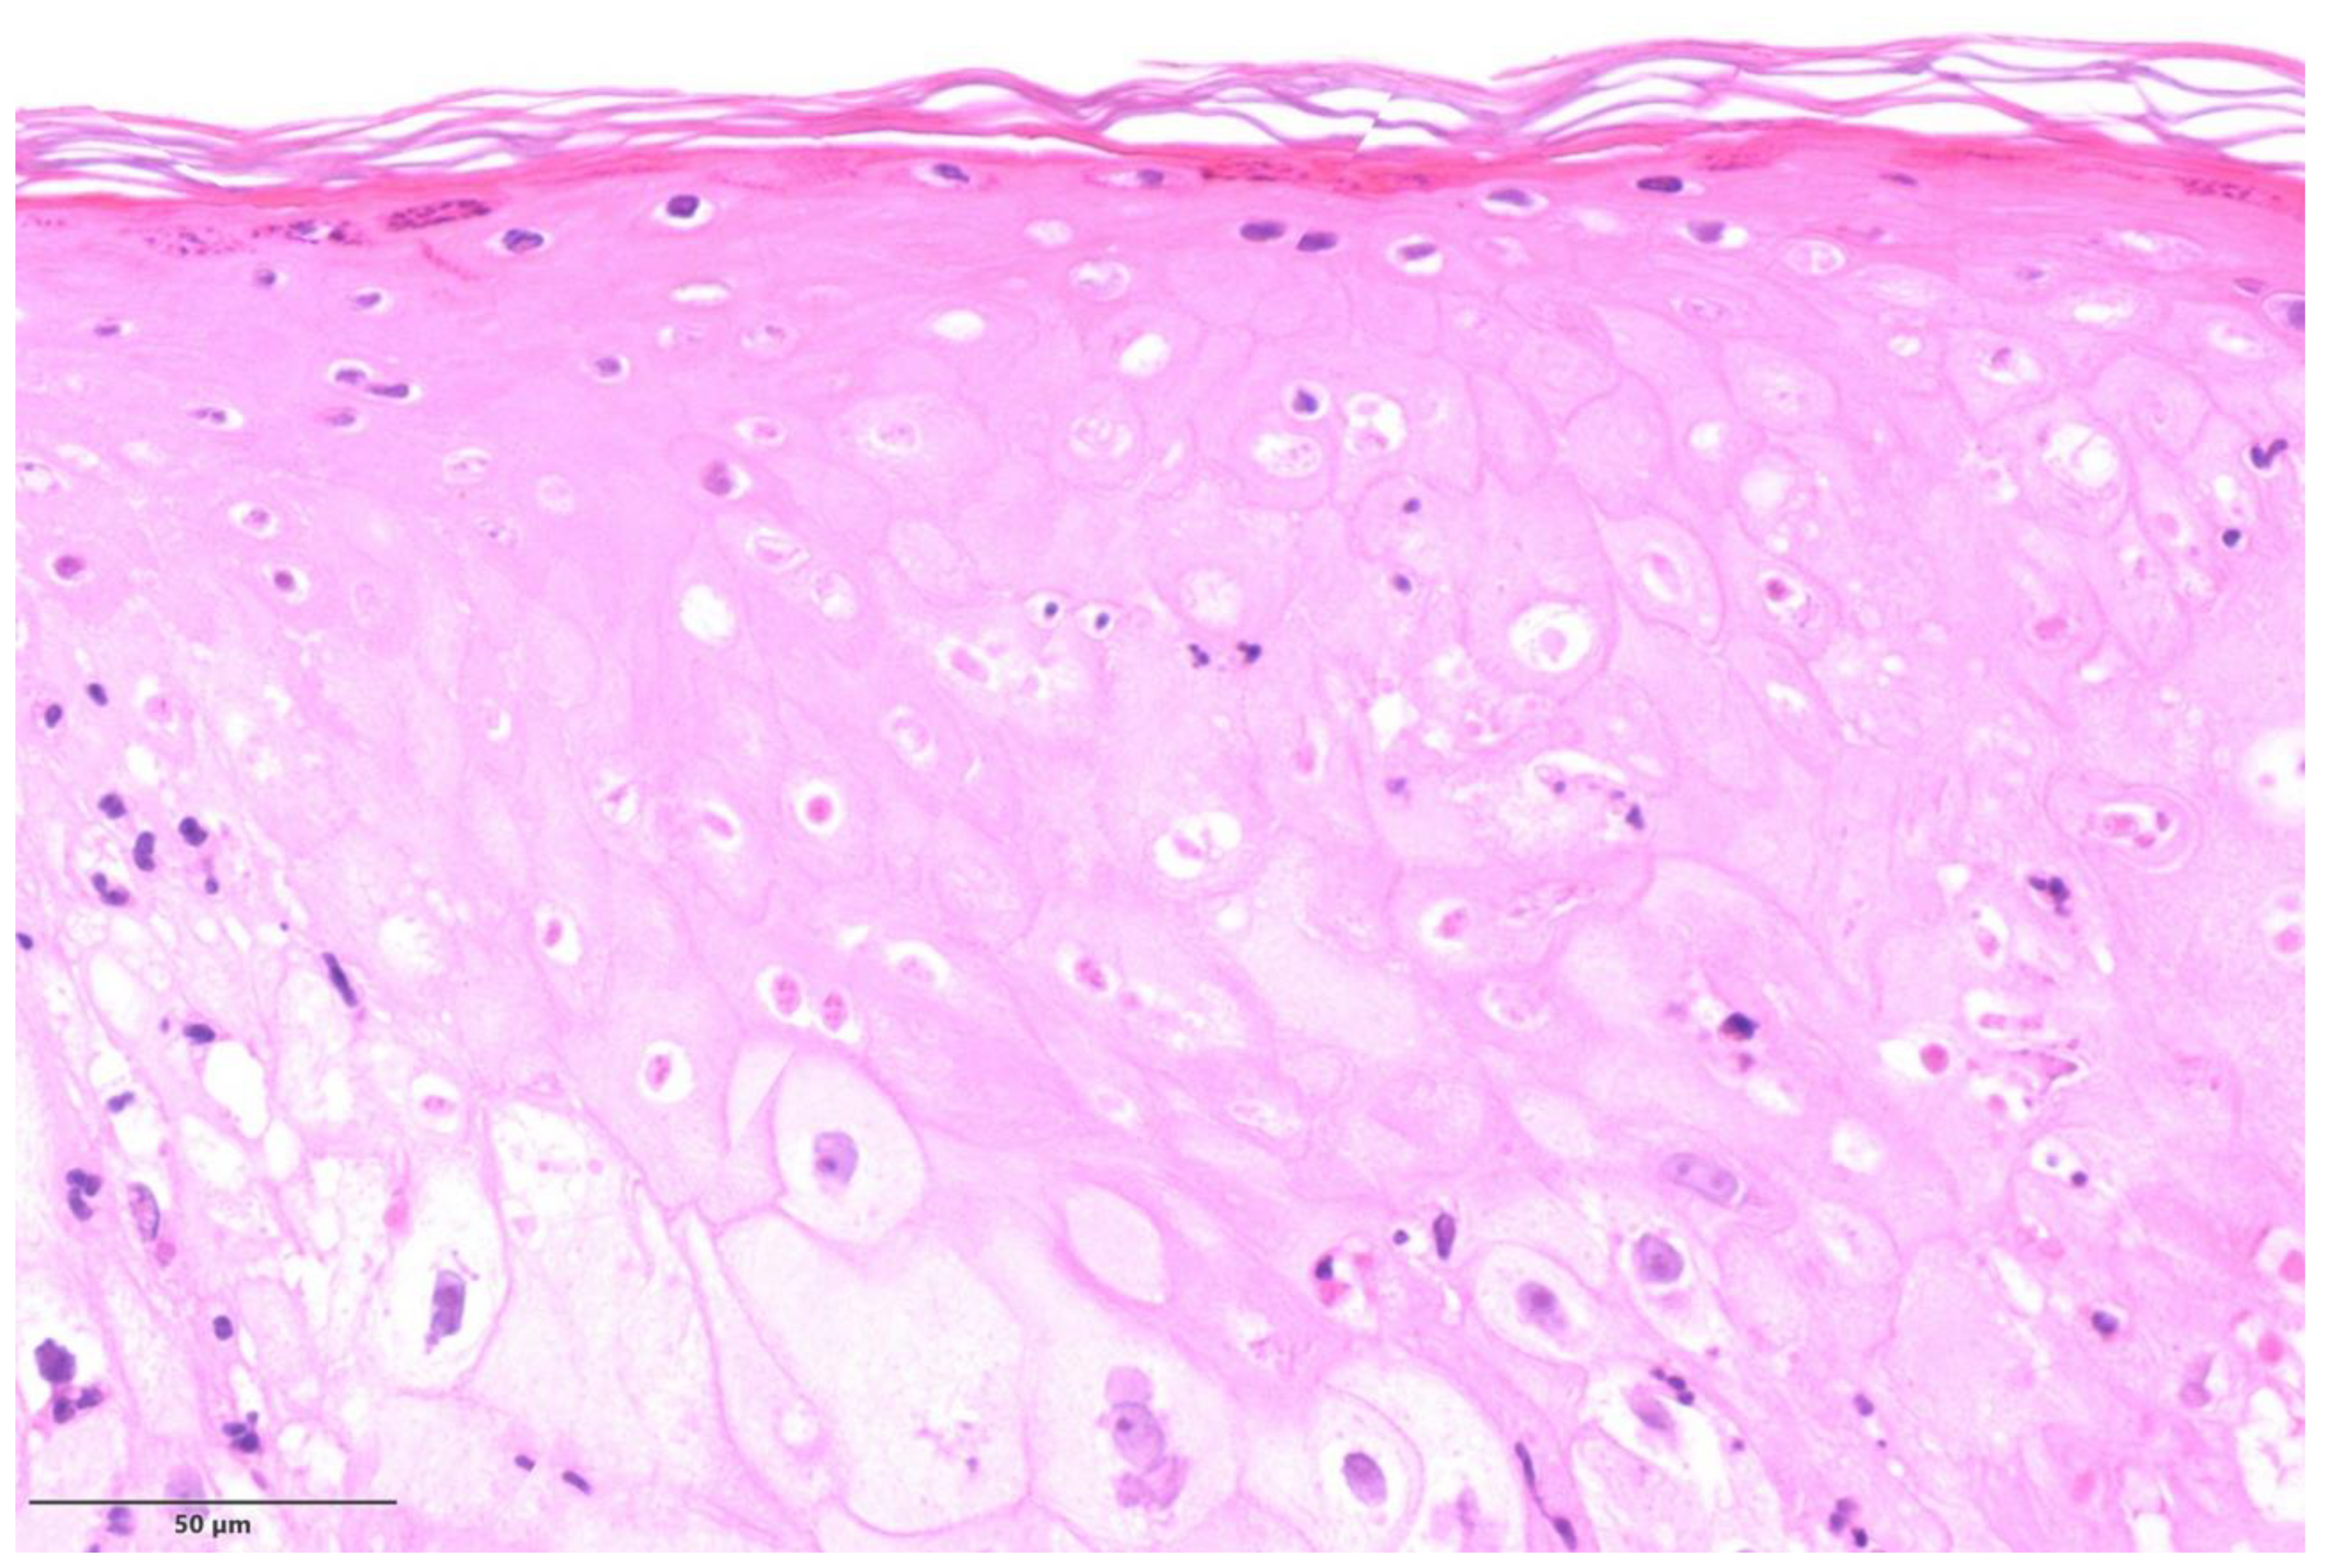

| 1 | Left thigh; penile shaft | Pustular stage | Multinucleated keratinocytes; occasional Guarnieri bodies; extensive ballooning; ground glass nuclei; degenerative modifications in the acrosyringial epithelium | Moderate perivascular and periadnexal with neutrophils |

| 2 | Penile | Pustular stage | Ground glass nuclei; ballooning; degenerative modifications in follicular keratinocytes | Mild perivascular lymphocytic infiltration |

| 3 | Groin, left shoulder | Pustular stage | Ballooning; occasional Guarnieri bodies; degenerative modifications in follicular keratinocytes | Moderate perivascular and periadnexal with neutrophils |

| 4 | Penile shaft | Pustular stage | Guarnieri bodies; ballooning; positive immunohistochemical staining for Treponema pallidum with spirochetes in cytoplasm of keratinocytes | Moderate perivascular and periadnexal with neutrophils |

| 5 | Pubic region | Vesicular stage | Ballooning; spongiosis and achantosis; degenerative modifications in the acrosyringial epithelium | Severe perivascular, interstitial, and periadnexal with neutrophils |